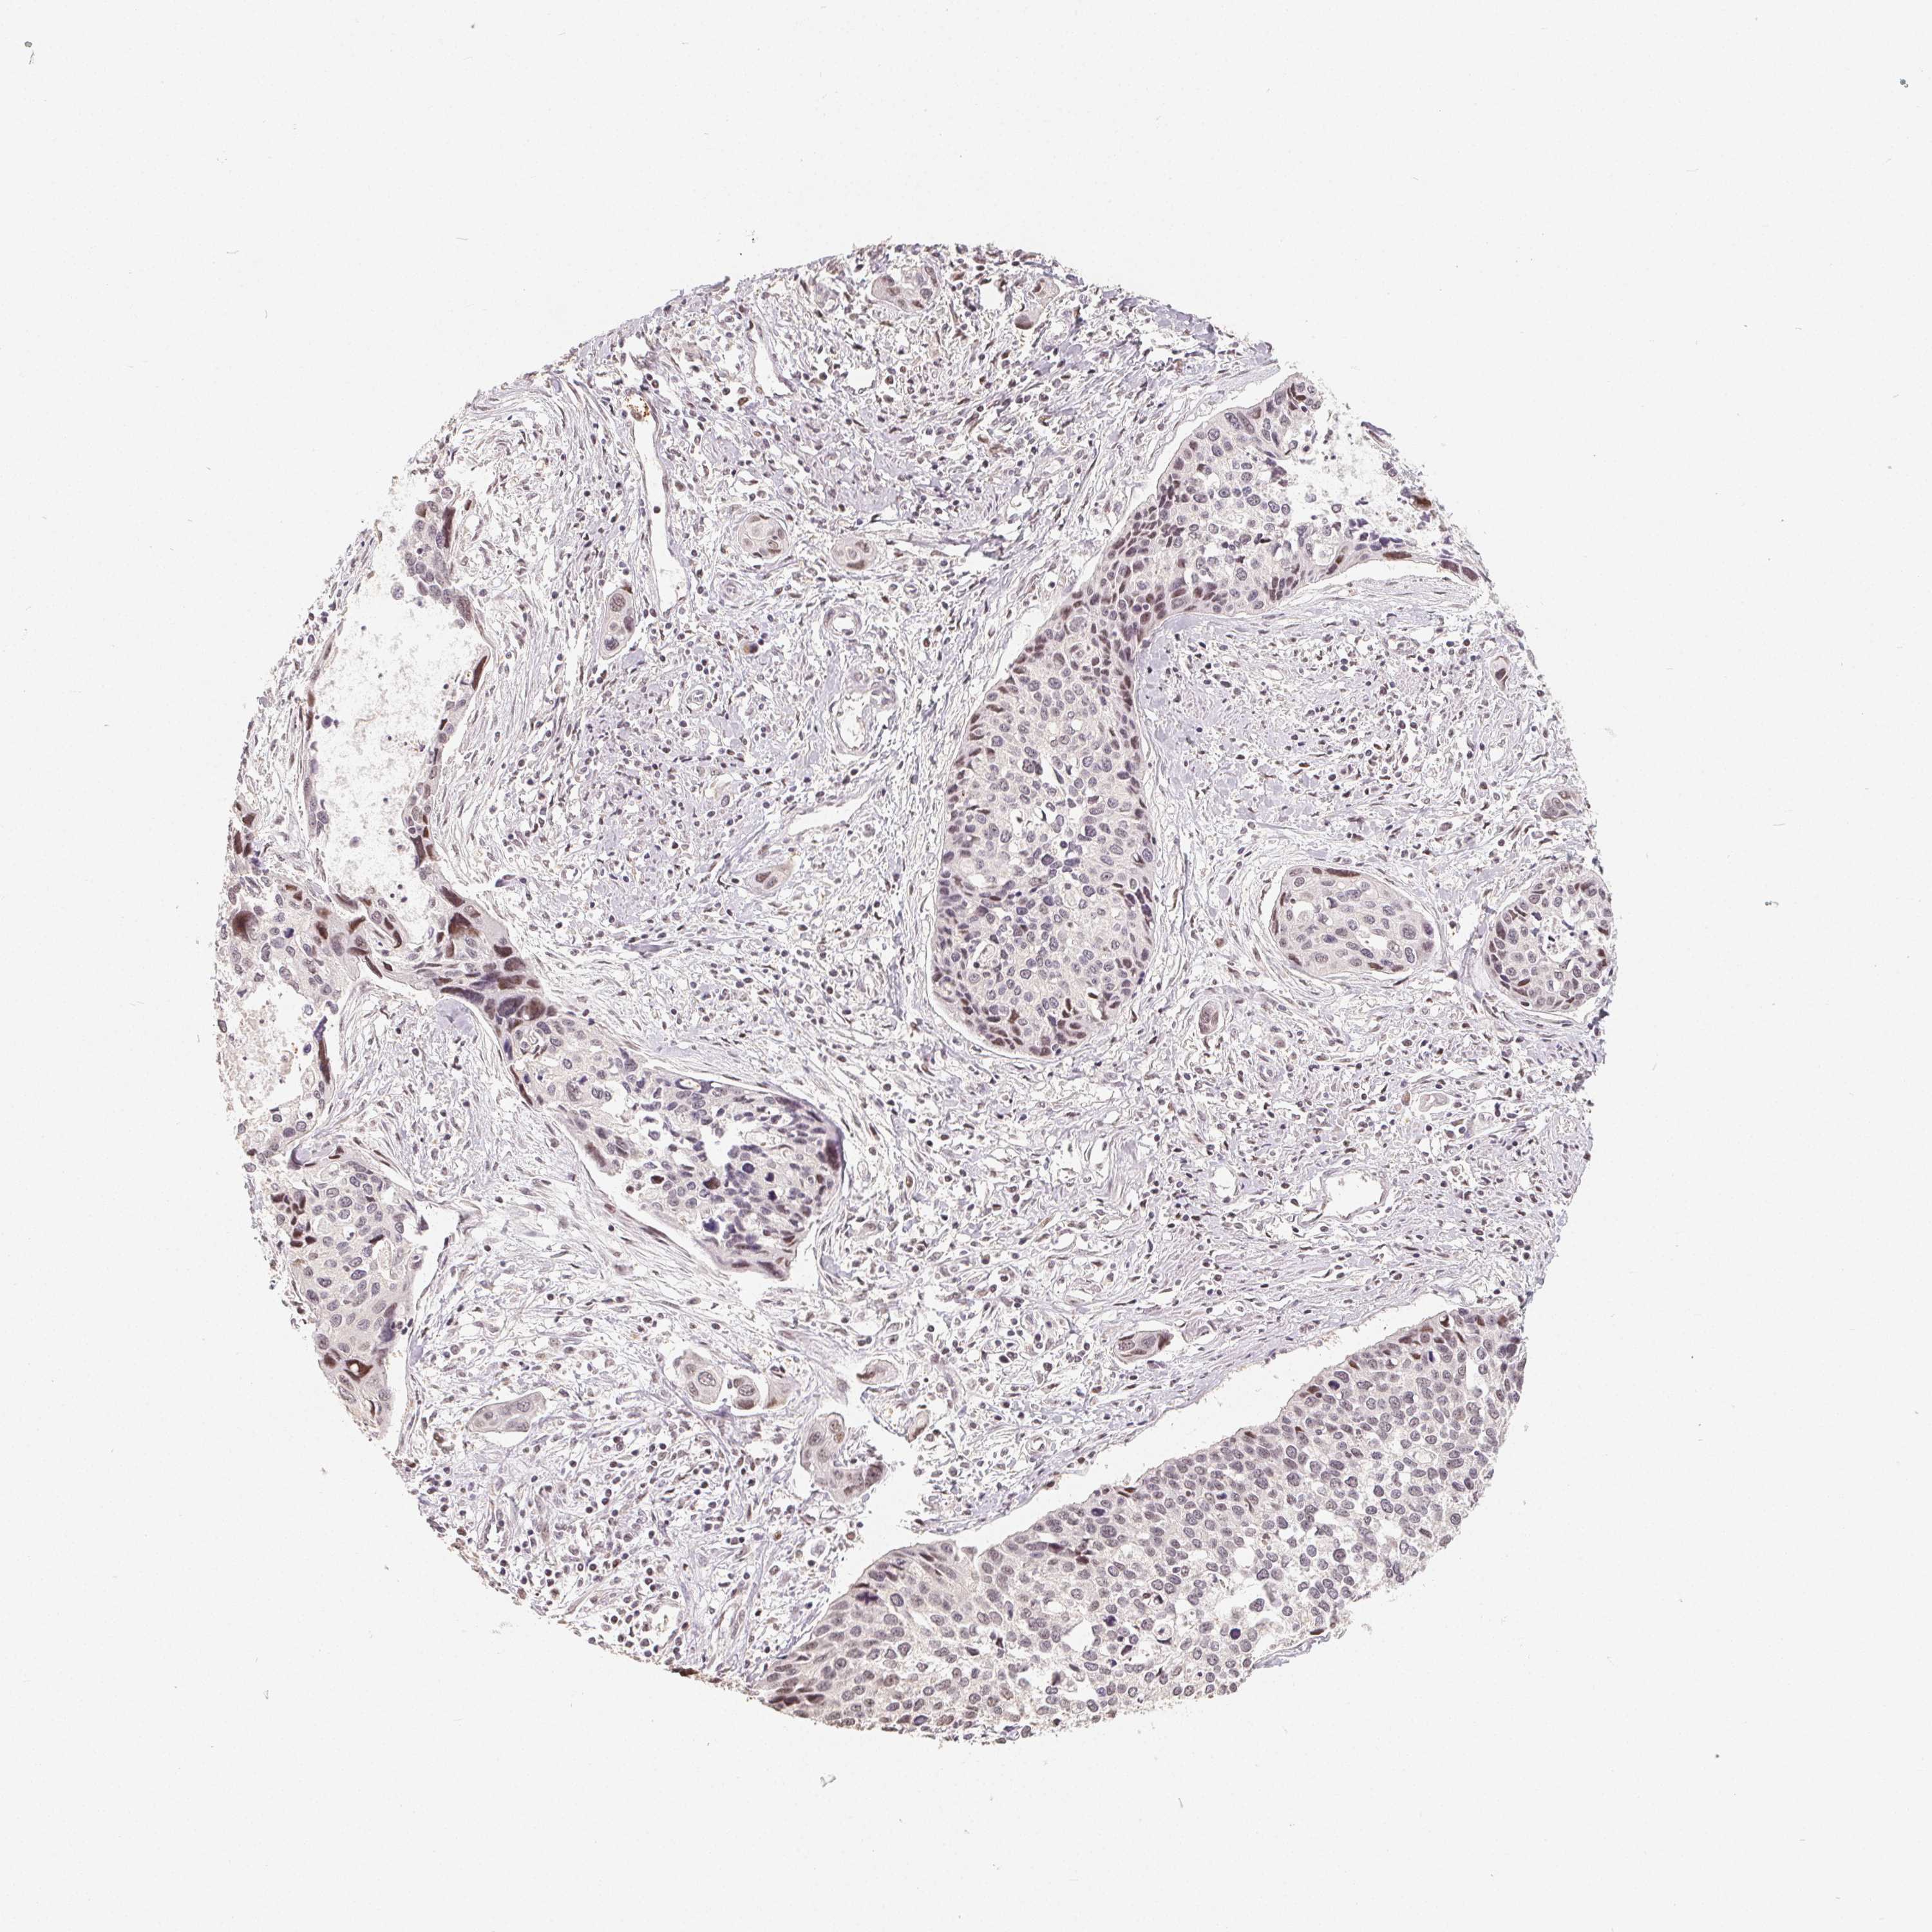

CERVICAL CANCER - Protein expressioni

A mouse-over function shows sample information and annotation data. Click on an image to view it in a full screen mode. Samples can be filtered based on level of antibody staining by selecting one or several of the following categories: high, medium, low and not detected. The assay and annotation is described here.

Note that samples used for immunohistochemistry by the Human Protein Atlas do not correspond to samples in the TCGA dataset.

Antibody stainingi

Antibody staining in the annotated cell types in the current human tissue is reported as not detected, low, medium, or high, based on conventional immunohistochemistry profiling in selected tissues. This score is based on the combination of the staining intensity and fraction of stained cells.

Each image is clickable and will lead to virtual microscopy that enables deeper exploration of all samples and also displays staining intensity scores, fraction scores and subcellular localization as well as patient and tissue information for each sample.

Antibody HPA054223

Staining

High

Medium

Low

Not detected

Intensity

Strong

Moderate

Weak

Negative

Quantity

>75%

75%-25%

<25%

None

Location

Nuclear

Cytoplasmic/membranous

Cytoplasmic/membranous,nuclear

Squamous cell carcinoma, NOS

Adenocarcinoma, NOS